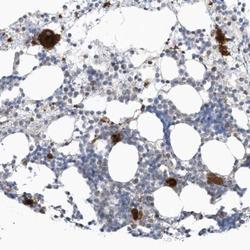

Supportive validation

- Submitted by

- Novus Biologicals (provider)

- Main image

- Experimental details

- Immunohistochemistry-Paraffin: GPATCH3 Antibody [NBP1-82301] - Staining of human bone marrow shows cytoplasmic positivity in hematopoietic cells.